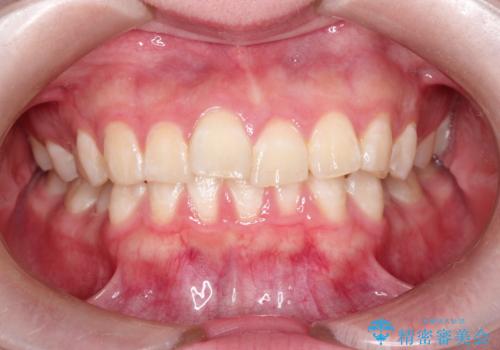

インビザラインで前歯のガタガタをきれいな歯並びへ

- 前歯のガタガタが気になるとのことで来院されました。

上顎の前歯の叢生があったのと、下あごの前歯が通常より1本欠損(先天欠損)していました。

上顎の歯と歯の間をわずかに削りスペースをつくり、並べる計画としました。インビザライン治療を選択されました。

しっかりとインビザラインを使用していただけたので、スムーズに治療を終了させることができました。